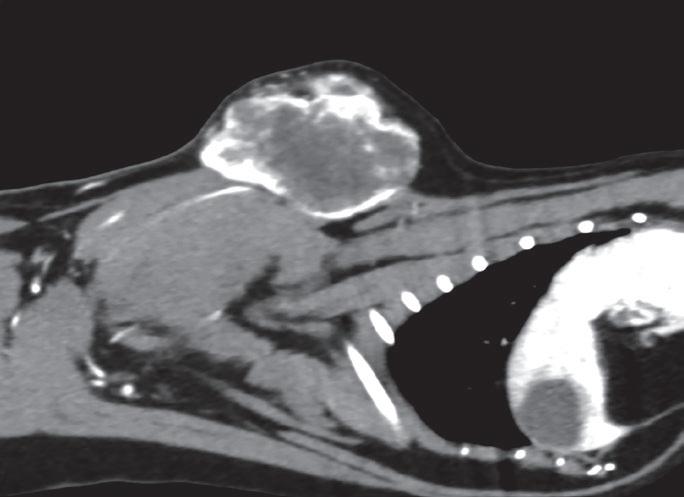

• Síndrome dígito-pulmonar felino como consecuencia de metástasis de neoplasias pulmonares primarias

• Abordaje clínico del quemodectoma de cuerpo aórtico